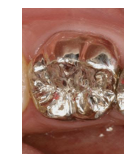

しかし、保険適用の銀歯だと、

咬む接触点は2~3点が限界です。

それは、材料的に適合精度に限界があり、

製作工程1回と少ないからです。

これでは、噛めるとは言えません。

見た目もよくありません。

銀歯